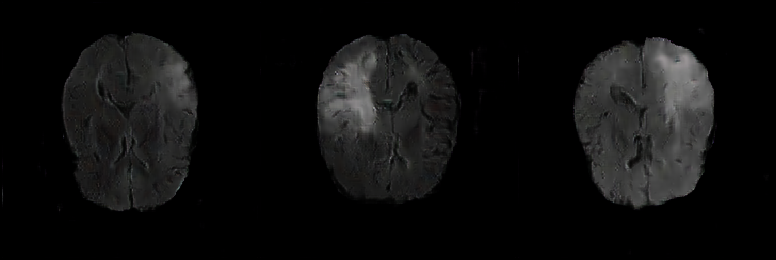

Generated Images Figure 5 shows the generated brain tumor FLAIR samples from -GAN-GP, PGGAN, and PGGAN-SSIM in AXI. The generated samples from all models look realistic and are close to the real images, where the white areas (Gliomas area) are concentrated and unified, indicating the training stability with gradient penalty. However, the samples from -GAN-GP are blurry, and the detailed brain features disappear since the loss of image information becomes serious when the image resolution increases in -GAN-GP. The generated samples from PGGAN and PGGAN-SSIM have clear and realistic brain features (FLAIR texture and tumor appearance) with diversity, which illustrates that PGGAN architecture is a well-suited model to generate brain MR images.